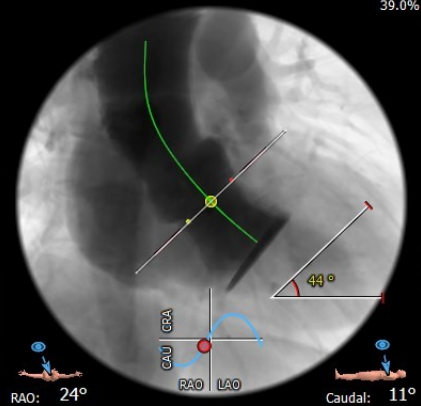

手术过程

全麻下建立双侧股动脉入路,以右股动脉为主;导丝跨瓣后置换猪尾导管,确定共平面。

图片

使用20mm球囊进行预扩,无腰征无反流。

预扩未见右冠显影,球囊主动保护。

通过支撑导丝,送入23mm SAPIEN 3瓣膜,使用独特调弯功能,保证安全过弓并成功跨瓣;调整至共平面角度,瓣膜到位,快速起搏下+1cc精准释放瓣膜。